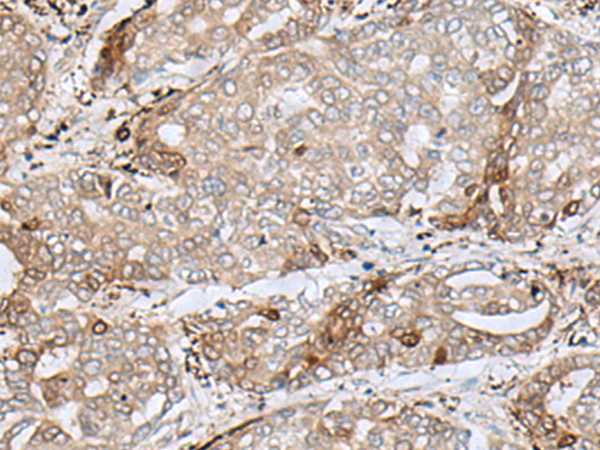

分类: 科研抗体货号: P02867别名: DHPR; PKU2; HDHPR; SDR33C1应用: WB,IHC反应种属: Human, Mouse, Rat